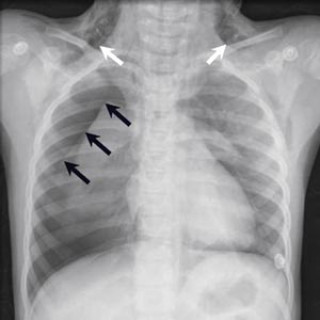

En 52 år gammel etnisk norsk mann ble innlagt i psykiatrisk akuttavdeling etter noen få uker med kraftig økende aktivitetsnivå. Han hadde vist markant endret atferd – blant annet hadde han satt seg fore å sykle åtte mil i kuldegrader og slaps. Ved innleggelsen var han irritabel og snakket fort og nærmest usammenhengende. Somatisk status presens ved innkomst samt orienterende nevrologisk status var normale. Vanlige blodprøver ved innleggelse, inklusive Hb, SR, hvite blodceller, kreatinin, natrium, kalium, ALAT, ASAT, ferritin, folat, kobalamin, FT4, TSH, var alle innenfor referanseområdet...